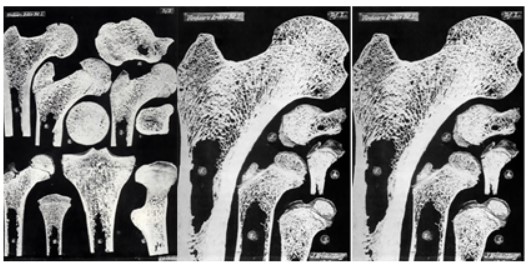

Además, el trabajo definitivo de Wolff se publicó en 1902 por lo que no pudo utilizar los rayos-X, ni el microscopio. Su tecnología se basaba en cortes con una sierra para cortar marfil, muy precisa, que le permitió hacer cortes finos, donde retiraba la grasa y la médula ósea con un chorro de agua [54] (Figura 6).

Figura 6. Cortes efectuados por Wolf